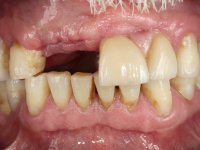

Paciente do sexo masculino, com 64 anos de idade, não fumador, recorreu á minha consulta após traumatismo do sector anterior. Os dentes 2.1 e 2.2 apresentavam extensas fraturas infra ósseas. Os dentes 1.2 e 1.1 apresentavam-se ferulizados com uma resina composta na zona inter-proximal. O dente 1.1 apresentava um tratamento endodôntico sofrível e um poste intra-radicular. O dente 1.2 estava vital e tinha uma extensa restauração da resina composta. Estando ferulizados, não foi possível avaliar o grau de mobilidade dentária de cada um dos dentes, mas o conjunto não tinha mobilidade. Após exame clínico e Imagiológico conclui-se que as raízes dos dentes 2.1 e 2.2 tinham extração indicada. O paciente estava reabilitado provisoriamente com uma prótese removível esquelética com 3 dentes. Apresentava algum comprometimento periodontal e os dentes mostravam as superfícies oclusais e incisais desgastadas. Higiene oral razoável.

O paciente sofreu um traumatismo e a fratura dos dentes fez com que fosse reabilitado de urgência com uma prótese esquelética. O que o trouxe a consulta foi a vontade de ter dentes fixos no sector anterior e abandonar a prótese removível. Inicialmente os dentes 1.2 e 1.1, que se apresentavam em muito mau estado, não estavam no plano de reabilitação do paciente. Posteriormente, com um novo traumatismo nestes dentes, levou a que o paciente optasse por querer reabilitar de forma fixa os 4 incisivos.